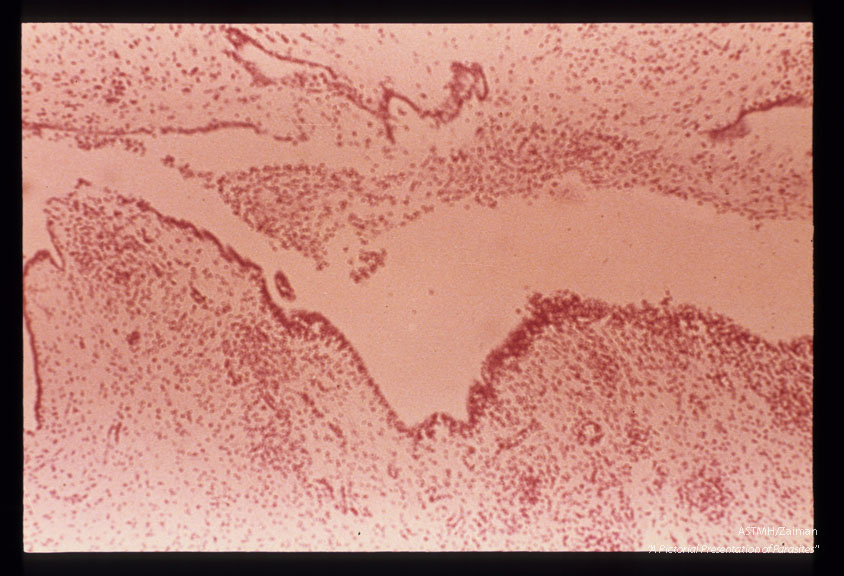

Encephalitis showing fourth ventricle not surrounded by necrosis. Instead, microglial nodule and watery inflammatory reactions accompany ulceratio in the ependyma. The foramina of Luschka and Magendi were open.

Toxoplasma gondii